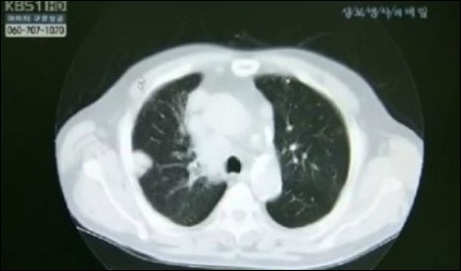

한국인 폐암 유형 1위인 폐선암을 재발시키는 유전자가 발견됐다.

서울아산병원 암병원 폐암센터 장세진·김형렬 교수팀은 13일 한양대의대와 서울대 자연과학대 연구팀과 공동으로 RB 유전자의 돌연변이가 폐암의 재발에 영향을 미친다는 사실을 발견했다.

한국인 폐암 유형 1위는 폐선암으로, 국내 폐암 환자의 40%에 달한다.

돌연변이 유전자의 발견으로 폐선암 재발 예측과 표적 약물치료 등 큰 도움이 될 것으로 기대를 모은다.